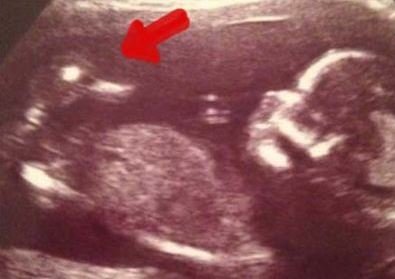

رویداد۲۴ این زن به همراه نوزادش ، یک اردک را نیز باردار است ! باز تصاویر سونوگرافی یک زن اردکی را کنار جنین در رحم مادر نشان داد که سبب تعجبب متخصصان شد . همیشه زنان باردار در زمان مراجعه با سونوگرافی مشتاقند بدانند نوزادشان دختر است یا پسر ، سالم است یا نه و اینکه چه شکلی است .

اما این زن باردار با دیدن نتیجه سونوگرافیش شوکه شد. وی بزرگترین شوک زندگی خود را زمانی تجربه کرد که برای سونوگرافی به پزشک مراجعه کرده بود اما تصویر نوزاد به دنیا نیامدهاش تنها چیزی نبود که او روی صفحه مانیتور دید.یک اردک در کنار کودکش این زن باردار و پزشکش را شوکه کرد.

این زن جوان بعد از سه سقط جنین برای بار چهارم مجدد باردار شده بود. کورتنی فنویک 28 ساله اهل نیوکاسل در زمان دیدن سونوگرافیش شوکه شد .او بعد از 3 سال مشکل بارداری و 3 بار آی وی اف که با مشکل مواجه شده بود، دوباره باردار شد. این بارداری با توجه به اینکه مادر دچار دیابت شد بسیار سخت بود. اما حضور این اردک اسباب خنده آنها را فراهم کرد.

وجود این اردک تنها این والدین بلکه دکتران دیگر را هم شگفتزده کرده بود وآنها میگفتند تاکنون نه چنین چیزی دیدهاند نه شنیدهاند.اکنون این نوزاد به دنیا آمده و در کمال صحت و سلامت به سر میبرد. هنگام زایمان خبری از اردک فوقالذکر نبود. اما دوستان به یاد آن اردک برای نوزاد به دنیا امده عروسک اردک آوردند. پزشکان هم نتوانستند توجیه مناسبی برای حضور اردک پیدا کنند.